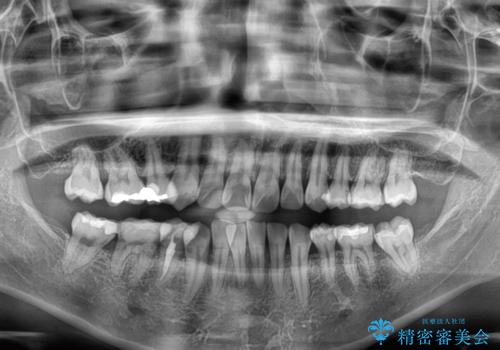

- 上下前歯の後戻りを気にして来院された患者様です。

インビザラインでの治療を希望されていて、デコボコの程度が中等度であり、安価なパッケージにて対応可能と判断されたため、インビザライン・モデレートを用いて矯正治療を行うこととしました。